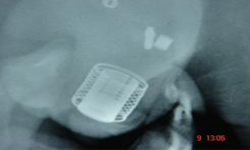

Micturating Cystourethrogram Cystometry

He was evaluated and investigated in detail and planned for artificial urinary sphincter. Preoperatively, micturating cystourethrogram, urodyanmic study, cystoscopy were done. The upper tracts were normal. There was no vesicoureteric reflux, stricture. Bladder capacity was 250 ml, maximum detrussor pressure was 30 cm of water and insignificant residual urine.